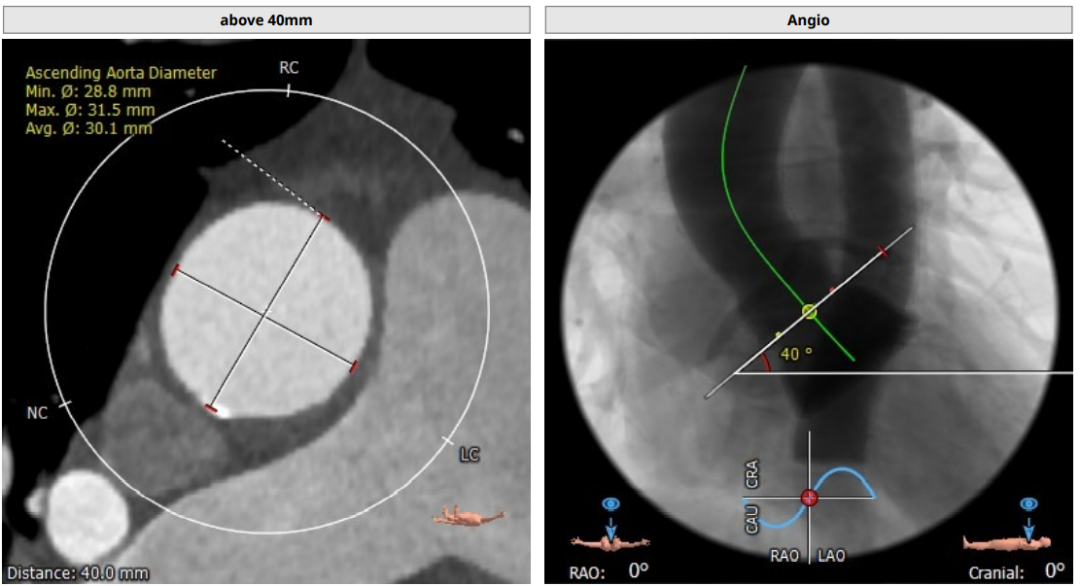

术前CT评估

升主动脉直径:30.1mm,心脏夹角:40度

• 三叶式主动脉瓣,窦部空间空间小,短径仅有21.5mm。

• 钙化轻度,集中在左冠瓣叶游离缘及无冠瓣叶游离缘。